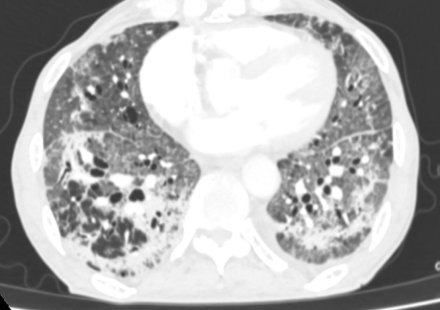

然而,病情的凶险程度远超预期,检查结果提示D-二聚体显著升高,CTPA提示右下肺动脉肺栓塞,肺部感染亦较前明显进展,病情进一步恶化。在呼吸与危重症医学科主任李芳芳带领下,团队迅速调整方案,加强抗凝与抗炎治疗。

胸部CT及CTPA